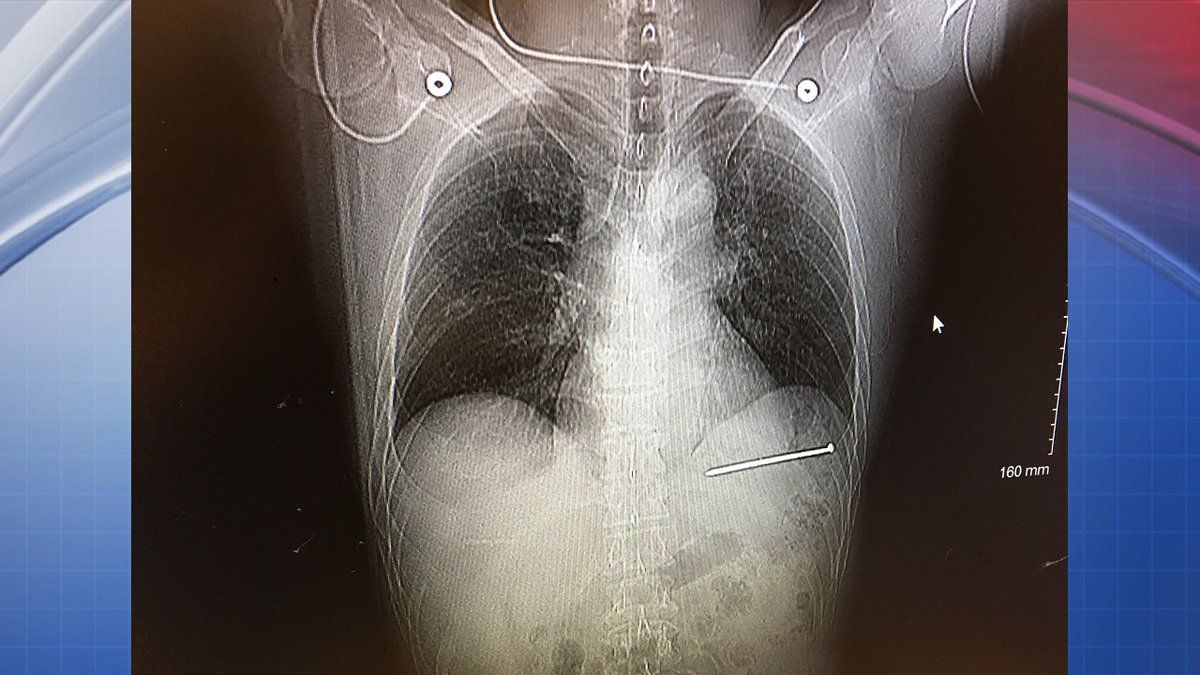

Conforme se fue quitando su sudadera, el hombre de 52 años dijo que se dio cuenta que alrededor de dos centímetros y medio del clavo de nueve centímetros sobresalía de su pecho.

“Podía ver el clavo moviéndose al mismo ritmo del latido de mi corazón”, explicó. Bergeson dijo que “el sentido común” fue lo que evitó que sacara el clavo de su pecho.

Luego de que le tomaran radiografías fue trasladado a un hospital en Green Bay, donde los cirujanos le retiraron el clavo.

El médico Alexander Roitstein confirmó que el clavo estaba a una fracción de pulgada de afectar una arteria importante. Dijo que fue difícil evaluar qué tan profundo había penetrado el clavo, pero que solo le dejó moretones y un agujero.